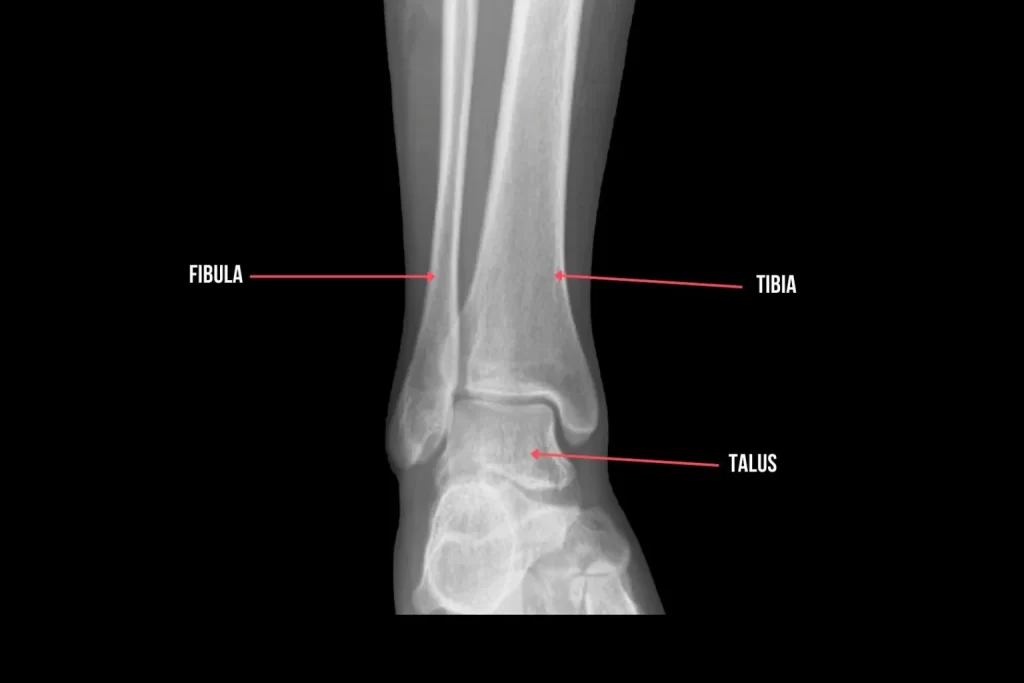

Introduction The ankle is an intricate structure that allows us to stand, walk, and move. Understanding the anatomy of the ankle is crucial in the